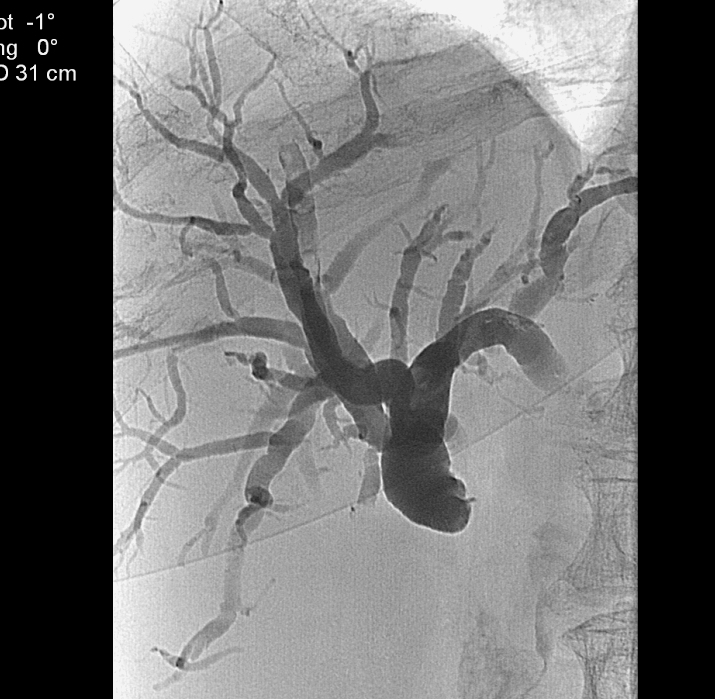

The CT-angiography and MR-angiography methods take nowadays over from the diagnostic selective catether hepatic angiographies. The catheter angiographies are performed in case of therapeutic (TAE – Figure 7, TACE, chemoperfusion) interventions and the traumatic liver injuries (selective embolisation) on these fields.

Figure 7: TAE (Transarterial Embolisation) of the liver with Lipiodol

Figure 27: HCC, TAE, agniography